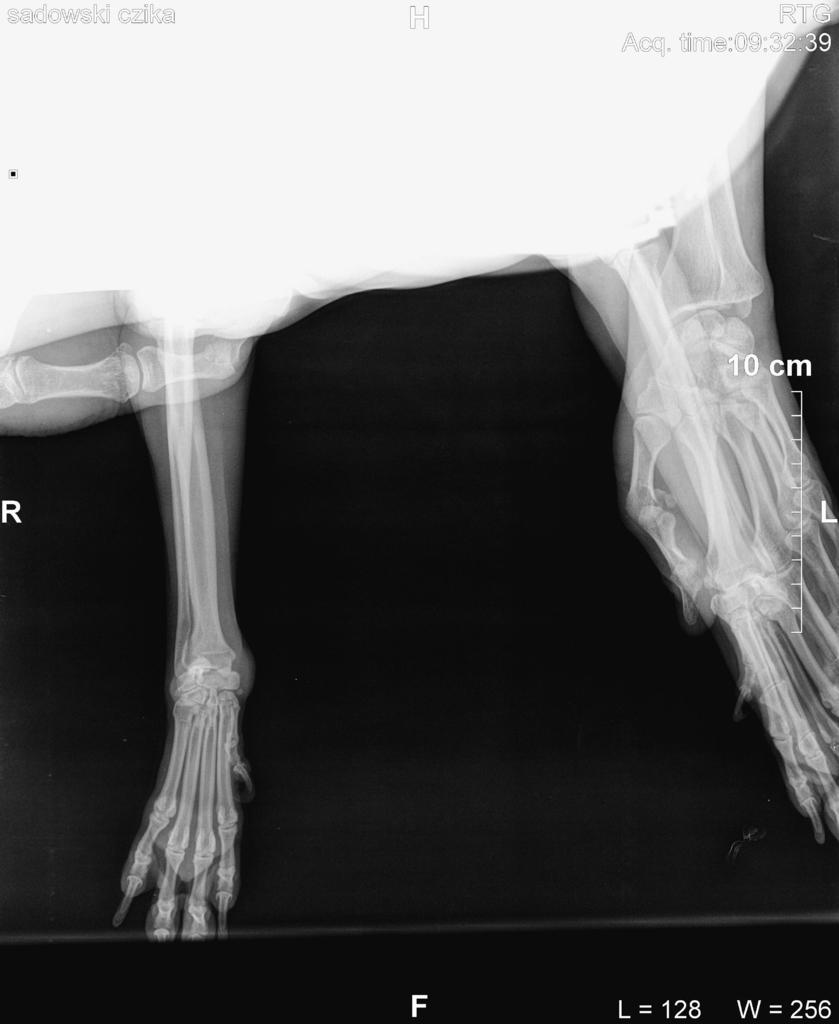

Dodalem w pierwszym poscie rtg z dzisiaj i rtg z 05.02.2014 (5miesiecy wczesniej to zdjecie w srodku)

[COLOR=#000000][FONT=Verdana]Witam, moja 10 letnia sunia ma taka wielka narosl na lapie.. ani to ja nie boli nie kuleje ani nic.. jest to miekkie, na poczatku jak bylo male byl robiony rentgen ale nie bylo zadnych zmian patologicznych.. macie moze pomysl co to moze byc? w zalaczniku dalem zdjecie lapy. kostniakomiesak a moze tluszczak? nie wiem co tym sadzic.. w zalaczniku dalem zdjecie lapy psa.. prosze o rady i pomoc ;)[/FONT][/COLOR][attachment=3445:11639.attach]